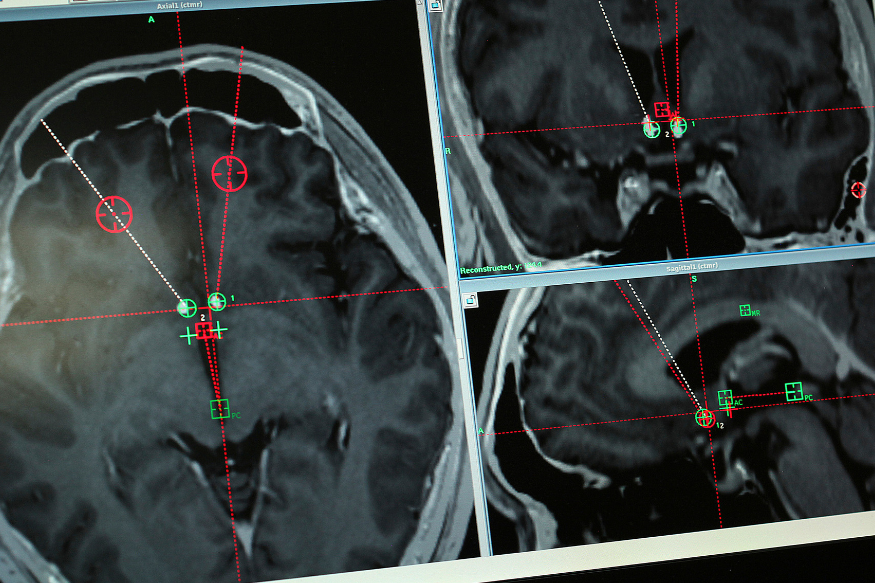

Brain scan of a methamphetamine addict with the path of electrodes that doctors at Ruijin Hospital in Shanghai, China implanted to stimulate an area of the brain associated with addiction.

At 9 a.m. on a grey October Friday in Shanghai, Dr. Li drilled through Yan's skull and threaded two electrodes down to his nucleus accumbens, a small structure near the base of the forebrain that has been implicated in addiction.